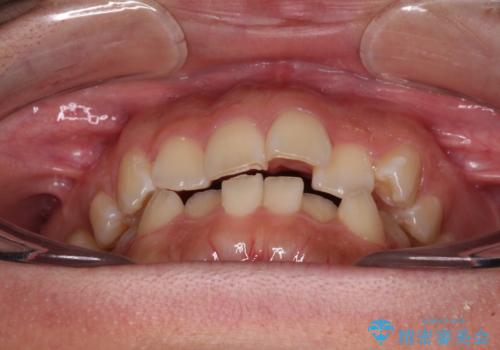

- 口元の突出感を気にして来院された患者様です。

診断の結果、上顎左右第一小臼歯4本抜歯により、叢生を解消するとともに口元を引っ込めていくことが望ましいと判断しました。

抜歯矯正による口元の改善にはワイヤー矯正が望ましいのですが、ダンサーとしての仕事を行っているため、インビザラインにて治療を行うこととしました。